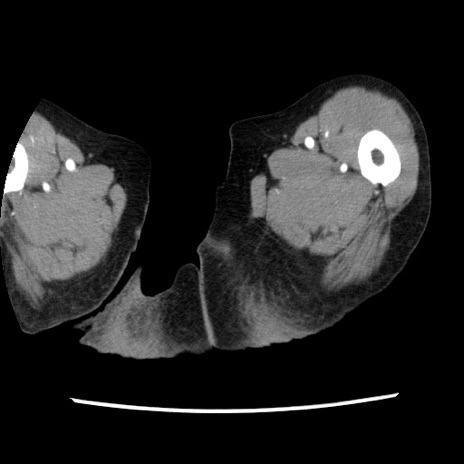

冠状断像

【症例】80歳代女性

【主訴】腹痛

【現病歴】8時間前から腹痛あり来院。

【既往歴】糖尿病、脂質異常症、子宮体癌にて子宮全摘術

【身体所見】意識清明・会話良好だが腹痛で苦悶様、全腹部にわたって反跳痛と圧痛あり

【データ】WBC 13600、CRP 0.14、LDH 224、CK 90